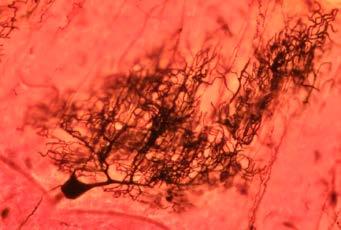

Humanidades: Cajal y el nacimiento de la Neurociencia moderna. Por Javier De Felipe

Homenajes a Ramón y Cajal. Clen College.